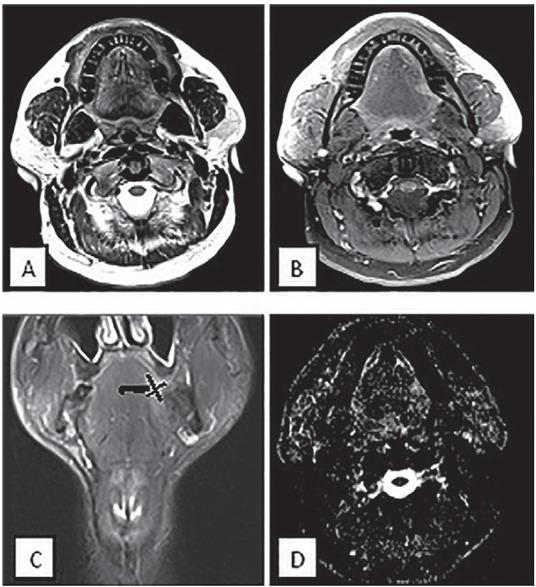

MRI of a male patient 65-years-old with small lesion at left hemi-tongue (T1N0) disease. (A) Axial T2 (B) Axial T1 fat suppression post contrast (C) T2 coronal (D) Axial DWI. MRI and elective dissected neck revealed no positive cervical lymph nodes spread. The vertical black line was drawn as a reference line connecting maximum tumour-mucosa junctions. Two horizontal lines were drawn perpendicular to the reference line. Tumour thickness is the sum of both of these horizontal lines and was determined as 5.5 mm. The thick black line between the tumour and the para-lingual space represented the para-lingual distance = 10.5 mm.